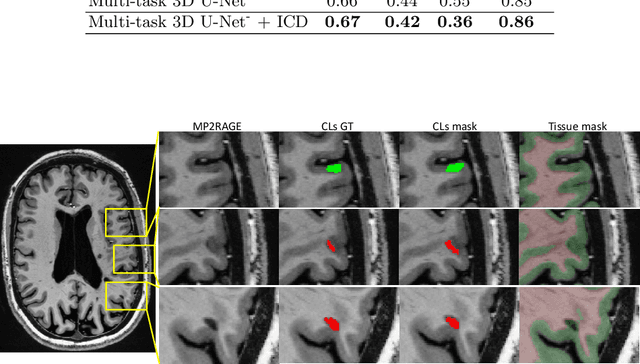

Abstract:The automated detection of cortical lesions (CLs) in patients with multiple sclerosis (MS) is a challenging task that, despite its clinical relevance, has received very little attention. Accurate detection of the small and scarce lesions requires specialized sequences and high or ultra-high field MRI. For supervised training based on multimodal structural MRI at 7T, two experts generated ground truth segmentation masks of 60 patients with 2014 CLs. We implemented a simplified 3D U-Net with three resolution levels (3D U-Net-). By increasing the complexity of the task (adding brain tissue segmentation), while randomly dropping input channels during training, we improved the performance compared to the baseline. Considering a minimum lesion size of 0.75 {\mu}L, we achieved a lesion-wise cortical lesion detection rate of 67% and a false positive rate of 42%. However, 393 (24%) of the lesions reported as false positives were post-hoc confirmed as potential or definite lesions by an expert. This indicates the potential of the proposed method to support experts in the tedious process of CL manual segmentation.